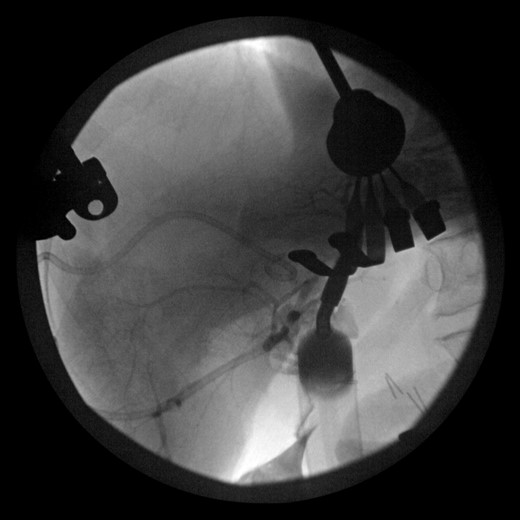

During this operation, the porta was dissected and the common and proper hepatic arteries were identified and preserved. We were unable to palpate the previously placed percutaneous biliary catheters due to the high placement above the hilum at the level of multiple clips. We transected the CBD distally and removed numerous clips, finally noting bile drainage, but were unable to identify a cholangiogram catheter. We then identified a second tubular structure more lateral to the duct. We elected to transect this tissue, identifying a second extrahepatic bile duct. The anterior percutaneous catheter was identified proximally within the duct. An on-table cholangiogram with fluoroscopy was performed noting two separate extrahepatic biliary systems, draining the right and left lobes of the liver, respectively (Figs 3 and 4). Both distal ducts were ligated to definitively close the orifice to the duodenum and prevent spillage. A Roux limb of jejunum was created and anastomosed in a retrocolic fashion to the two separate hepatic ducts at the level of the hilum. A drain was placed, and there was no evidence of bile leakage.

Intraoperative cholangiogram of the right ductal system through the extrahepatic right CBD.